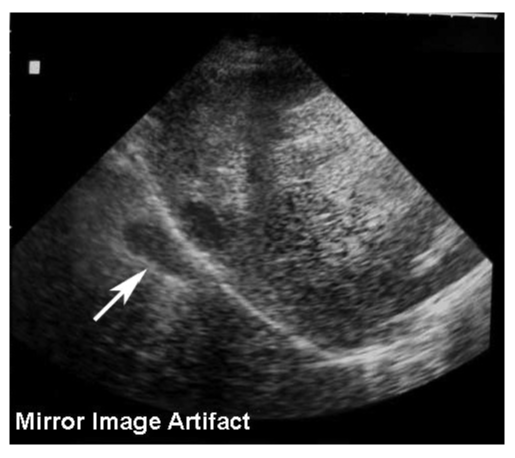

Mirror image artifact. Here the diaphragm acts as an acoustic mirror and maps a duplicate image of the region above it to the region below and here, to the left of the diaphragm. It is an artifact because structures appear at deeper depths where they don't exist.

_page_22.png?sfvrsn=e8a1cf20_2)